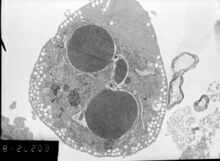

Label-free live cell imaging, time-lapse microscopy, flow fluorocytometry, and transmission electron microscopy can be used to compare apoptotic and necrotic cells. There are also various biochemical techniques for analysis of cell surface markers (phosphatidylserine exposure versus cell permeability by flow cytometry), cellular markers such as DNA fragmentation[77] (flow cytometry),[78] caspase activation, Bid cleavage, and cytochrome c release (Western blotting). Supernatant screening for caspases, HMGB1, and cytokeratin 18 release can identify primary from secondary necrotic cells. However, no distinct surface or biochemical markers of necrotic cell death have been identified yet, and only negative markers are available. These include absence of apoptotic markers (caspase activation, cytochrome c release, and oligonucleosomal DNA fragmentation) and differential kinetics of cell death markers (phosphatidylserine exposure and cell membrane permeabilization). A selection of techniques that can be used to distinguish apoptosis from necroptotic cells could be found in these references.[79][80][81][82]